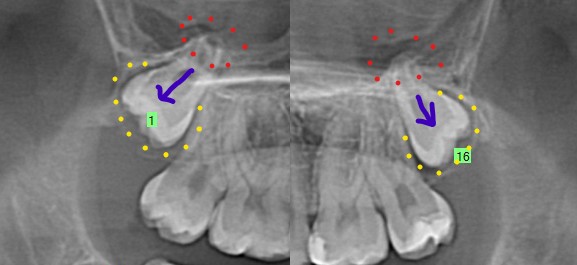

Upper Wisdom Teeth

For both upper wisdom teeth (#1,16), the roots have developed but the roots tips are still developing (red dots) and the crowns are not directed towards the teeth in front of them (purple arrow). They also don’t have enlarged follicles (yellow dots). Both of these indicate a lower risk for future root resorption or pathology. It is hard to predict if these teeth will stay impacted or potentially drift downwards and erupt into the patients mouth in the future. Having these teeth removed in the patient’s teenage years decreases the risk of future issues with them and also will result in better bone formation in the area where the wisdom teeth were. If these teeth require removal at a later age, the roots become more developed and occasionally develop hooks that makes removal more difficult and the bone around the wisdom teeth becomes denser. Removal at a later age also can result in poor bone regeneration in the space left by the tooth extraction which may ultimately affect the health of the tooth in front of it. There is no strong recommendation to either remove or leave the tooth in place for the upper wisdom teeth.